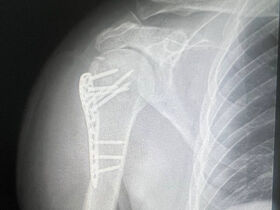

Эндопротезирование сустава ― это единственный способ не потерять способность к полноценному движению для людей, у которых сустав был серьезно поврежден или поражен тяжелой болезнью. Во время операции хирург удаляет костные и хрящевые ткани, которые уже не могут полноценно выполнять свою функцию, и устанавливает искусственный протез плечевого сустава. Современные эндопротезы изготавливаются из устойчивых к износу, гипоаллергенных материалов, поэтому после эндопротезирования пациент на протяжении многих лет может вести активный образ жизни.

Операция проводится натощак, под общим наркозом. Во время хирургического вмешательства суставные поверхности удаляются полностью или частично, соответственно выполняется тотальное или однополюсное эндопротезирование.

Если у пациента повреждена вращающая манжета, ему проводят реверсивное эндопротезирование плечевого сустава, что позволяет восстановить способность к вращательным движениям и поднятию руки. Компоненты эндопротеза присоединяются к костям с помощью специального цемента или бесцементным способом.